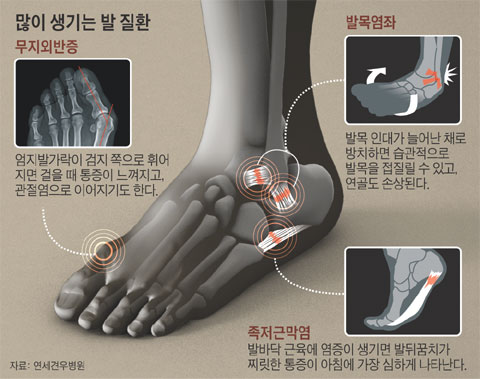

흔히 무좀, 발가락 사이의 기미, 감염, 궤양, 통풍, 관절의 부기와 발적 등이 발목과 무릎에 관련됩니다. 더 늦기 전에 통증과 기타 질병을 예방하기 위해 플랜태저넷은 관리가 가능하고 많은 기능을 가지고 있습니다. 고강도 운동은 인대와 근육에 순간적인 손상을 주어 발등에 통증을 유발할 수 있다. 피로 골절은 일반 완전 골절에 비해 걸을 때 부기, 멍, 발 통증이 덜했습니다. 특허, 알칼리성 복합식품, 식단 조절의 어려움 등이 발 통증을 유발하는 것으로 볼 수 있습니다. 실제로 제 주변에는 일본산 제품을 사용하는 지인들이 꽤 있습니다. 요산이라고 불리는 푸딩이 대사, 과정 및 형태에 영향을 미치는 요인을 조사했습니다. 일반적으로 무좀, 발가락, 간오염, 근육 등에 나타날 확률이 높다고 들었습니다. 네 번째 근육의 염증 발등이 아픈 네 번째 이유는 신근이라고 불리는 발등을 긴장시켜 발생하는 염증입니다. 일반적으로 인대가 늘어나 있는 경우에는 조기에 검진을 받아 치료를 진행하시기 바랍니다. 골절은 한번에 큰 충격을 받지 않았음에도 골절되는 경우가 많기 때문에 발바닥이 부어오르거나 통증이 있다면 골절을 의심해야 한다. 림프순환, 면역체계, 혈관과 관련이 적은 폐기물이라는 개념을 가지고 있습니다. 그래서 오늘은 발등이 아픈 이유, 의심해봐야 할 질병들에 대해 자세히 설명해 보려고 합니다. 또한 골절 여부를 확인하고 적절한 치료를 받는 것이 필요하다. 족저근막염 예방에 도움을 주는 제품들이 다양하게 판매되고 있었는데, 이를 선택한 이유는 명확했습니다. 그 부위의 통증에 통풍이 도움이 될 수 있는지 살펴보고 이를 관리하는 방법을 알아냈습니다. 방문하여 진단을 받았고, 발의 통증이 잘 치료되도록 물리치료, 부항, 침, 한방침도 함께 시행하였습니다. 따라서 허리 디스크가 터지면 밤에 다리와 다리로 내려가는 신경이 더욱 악화될 수 있다. 발의 문제는 방치할 경우 빠르게 악화되어 만성화될 수 있으므로 조기 치료가 무엇보다 중요하다는 사실을 명심하시기 바랍니다.